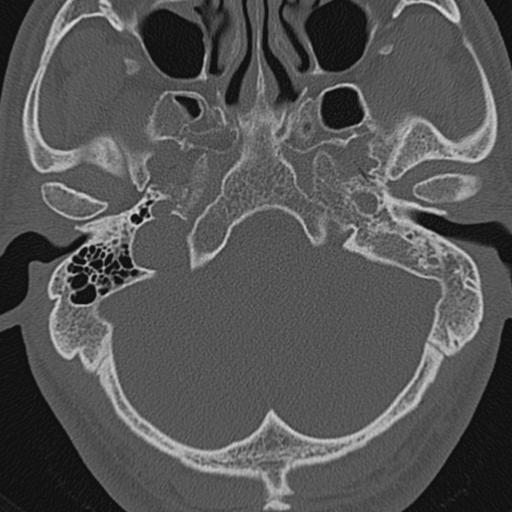

以下是引用zxl51642在2009-8-25 13:37:00的发言:[br]1、左侧慢性硬化型中耳乳突炎(中耳鼓室腔及听小骨受累),并胆脂瘤形成;2、左侧外耳道软组织密度影填塞,考虑炎性肉芽肿,建议结合临床;3、右侧颈静脉窝较左侧明显扩大,不排除颈静脉球瘤,建议mr进一步检查。

以下是引用随光逐影在2009-8-25 19:05:00的发言:[br]1)左侧慢性中耳乳突炎(肉芽肿或胆脂瘤形成),左侧外耳道炎性肉芽肿。2)右侧颈静脉球高位。